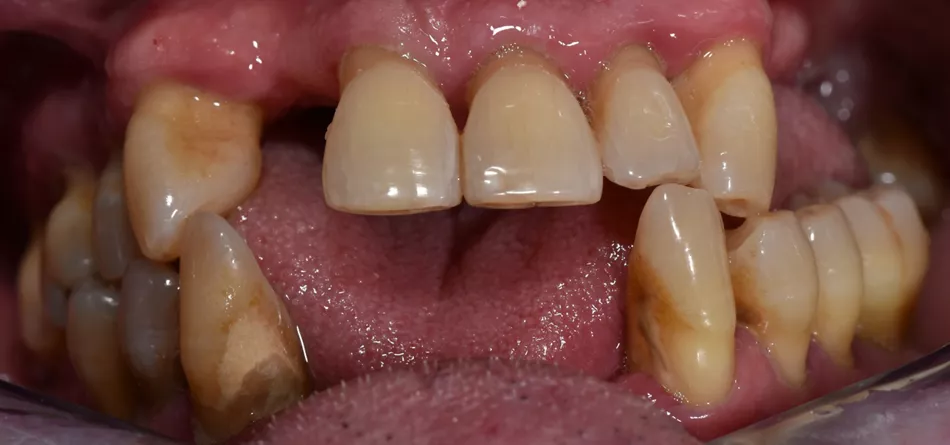

A 55-year-old patient with no medical history or ongoing treatment, a non-smoker, presents for consultation with the desire to address aesthetic and functional issues. The examination reveals missing teeth, a disturbed occlusal plane, extrusions, and versions of residual teeth.

2. Aesthetic and functional deficit due to tooth loss.